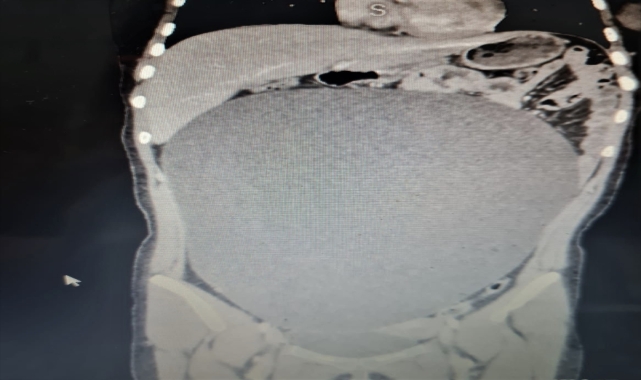

ZEKERİYA KARADAVUT - Aksaray'da yaralı kurtulduğu trafik kazası sonrasındaki muayenede tespit edilen karnındaki yaklaşık 8 kilogramlık kitle başarıyla alınan hasta, sağlığına kavuştu. Lise öğrencisi B.G'ye (17), 25 Ağustos'ta Ankara Caddesi'nde halk otobüsü çarptı. Kaza nedeniyle vücudunun çeşitli yerlerinde kırıkları olan B.G, Aksaray Eğitim ve Araştırma Hastanesine kaldırıldı.Burada yapılan tetkiklerde genç kızın karın bölgesinde anormal biçimde büyümüş bir kitle olduğu tespit edildi.Hastanenin Çocuk Cerrahi Bölümü Uzmanı Dr. Öğretim Üyesi Ayşe Betül Öztürk tarafından acil şekilde ameliyat edilen B.G'nin karnından 60 santimetre çapına ulaşan yaklaşık 8 kilogramlık kitle başarıyla çıkarıldı.- "Neredeyse bu kitle tüm karnını kaplıyordu"Operasyona ilişkin bilgi veren Öztürk, AA muhabirine, 17 yaşındaki kız çocuğunun yaralanıp acil servise getirilmesiyle sürecin çok hızlı ilerlediğini söyledi.Serviste hastanın tedavisine başladıklarını, tomografisinde karnında oldukça büyük bir kitle olduğunu gördüklerini anlatan Öztürk, şöyle konuştu:"Neredeyse bu kitle tüm karnını kaplıyordu. Aileyle görüşerek hızlı şekilde ameliyat kararı aldık. Ameliyat çok başarılı geçti. Sağ yumurtalık kaynaklı kitle başarılı şekilde alındı. Kitlenin organları sağa ve sola doğru sıkıştırdığını gördük. Kitle akciğer zarıyla temas halindeydi. Alt taraftan idrar torbasından akciğer zarına kadar uzanan oldukça büyük bir kitleydi. Bu kitle çok büyümüştü, eğer öğrenilmeseydi patlayabilirdi. Bu durumda da hayati tehlike ortaya çıkabilirdi. Daha da büyüyebilir ve ameliyat edilemez bir duruma gelebilirdi."Ailelere çocuklarının mutlaka ara ara karın muayenelerini yapmalarını önerdiklerini vurgulayan Öztürk, "Eğer anormal bir büyüme görüyorsak, mutlaka doktora danışmalıyız. Aileler için zayıf bir çocukta göbek varsa, mutlaka bu dikkat çekici olmalı"- Aile de kitleyi öğrenince çok şaşırdıAnne Reyhan G. ise kızında hiçbir belirti olmadığını, kitleyi fotoğrafta görünce çok şaşırdığını ifade etti.Kızının kitleyi ne zamandır taşıdığını bilmediklerini belirten Reyhan G, şunları kaydetti:"Bütün organlarına baskı yapmış. Çok şükür patlamadan kurtulduk. Kızım uzun zamandır diyet yapıyordu ancak bir türlü karın bölgesinden kilo veremiyordu. Hep merak ediyordu neden kilo veremediğini. Bu kitle yüzünden demek ki kilo veremiyormuş. Özellikle karnında şişlik olan aileler çocuklarının karın muayenelerini kesinlikle ertelemesin. İlk işim diğer çocuklarımı da muayene ettirmek olacak."